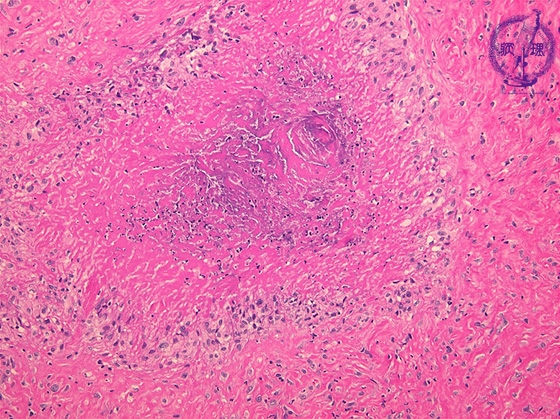

- ★(2)Rheumatoid arthritis

Microscopic view (HE; middle power view): Histology of rheumatoid nodules. These frequently occur at the subcutaneous tissue of extensor of elbow and knee, and the joint of hand, foot and fingers. Epithelioid cells are arranged at palisaded or radicular manner, and surrounding central necrosis.